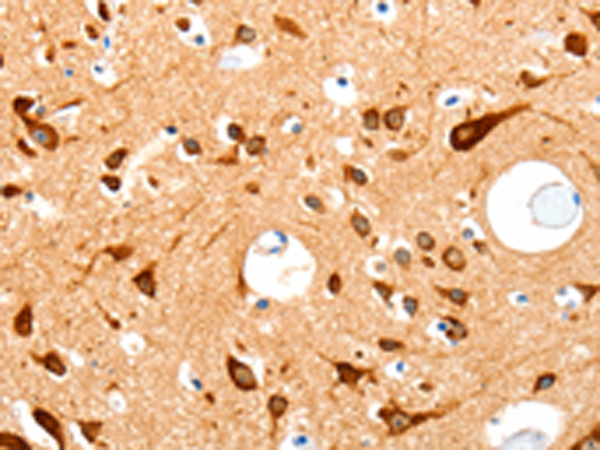

分类: 科研抗体货号: P11000别名: MDS, LIS1, LIS2, MDCR, PAFAH应用: IHC反应种属: Human, Mouse, Rat